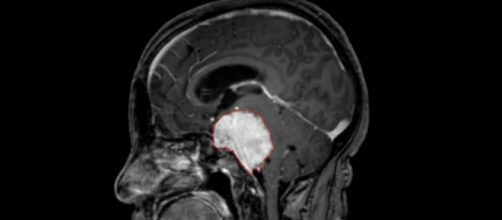

El desarrollo de metástasis cerebral es una complicación casi siemprefatal para más de la mitad de los pacientes cuyo tumor primario se extiende al cerebro. Un nuevo estudio presentado en el Congreso Europeo del Cáncer que se celebra en Viena demuestra que las metástasis cerebrales comparten algunas características genéticas con tumores primarios de los que se originaron pero también tienen mutaciones genéticas únicas. Tal heterogeneidad genética indica una divergencia en las vías evolutivas de metástasis y tumores primarios que podrían ser la base de la diferente sensibilidad a los fármacos de las metástasis cerebrales.

Las metástasis cerebrales suelen venirde cáncer de pulmón, de mama, carcinoma renal o melanomas. Para ver estas diferenciasgenéticasel equipo de investigación realizó toda la secuenciación del exoma de tres muestras de tejido, tumor primario, metástasis cerebrales y tejido normal.

En el estudio participaron 86 pacientes con cáncer de pulmón, cáncer de mama o deriñón. En todos los casos, los investigadores observaron que si bien el tumor primario y las metástasis compartían algunas mutaciones, las metástasis cerebrales presentan en más de la mitad de los pacientes estudiados (el 53%) nuevas mutaciones no relacionadas con las de los tumores primarios.